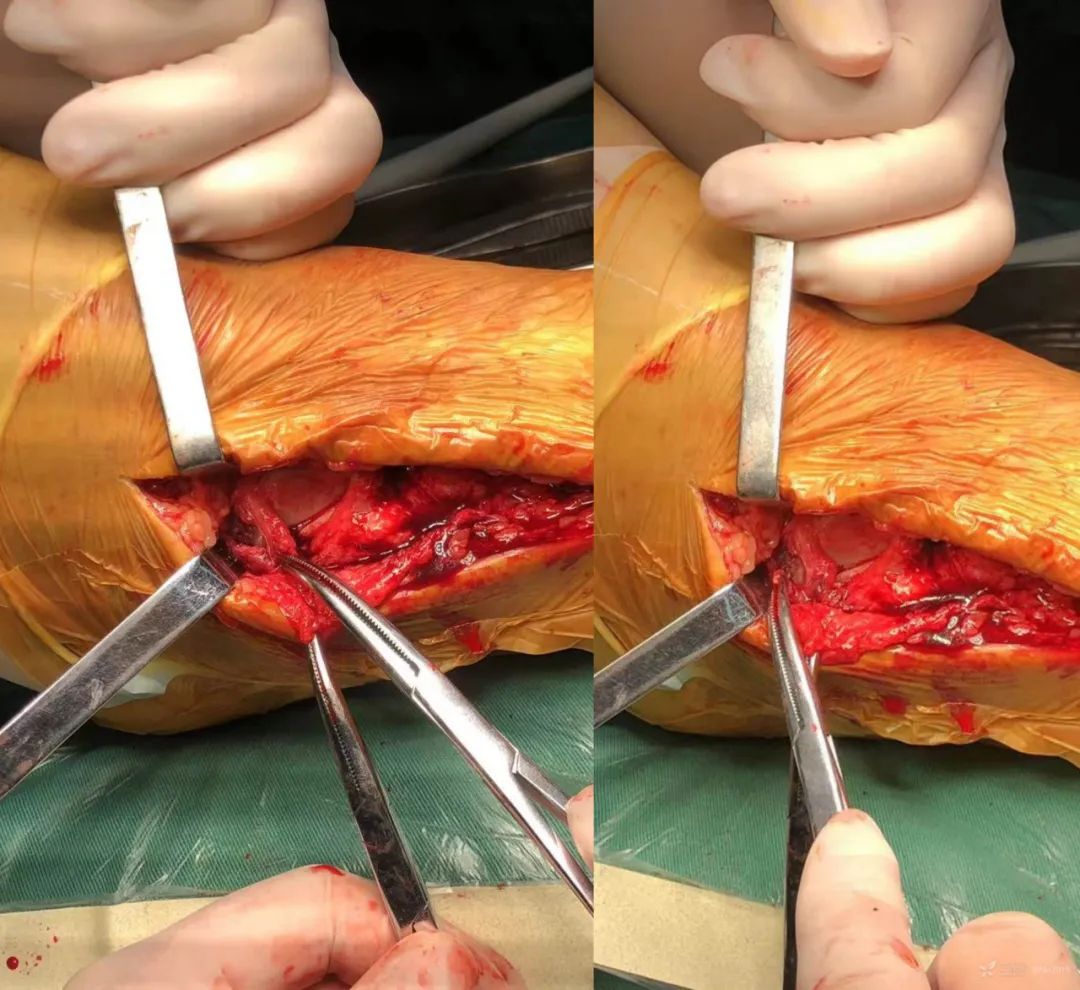

这是一例三踝骨折的患者。

术中发现三角韧带深层矢状面撕裂

术中将骨折与韧带损伤一一处理。